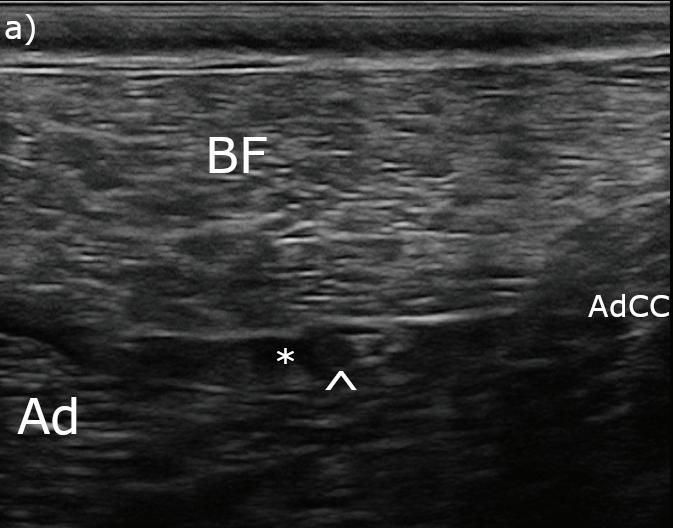

Tras rasurar y desinfectar la EPD, se realizó un bloqueo ecoguiado de los nervios ciático (Fig. 3A) y safeno (Fig. 3B) en el fémur medio,6 con bupivacaína 0,5 % (Bupivacaina 5 mg/ml, B Braun, Rubí (Barcelona), España; 0,1 ml/kg/nervio) y dexmedetomidina (1 μg/kg/nervio). Para ello se utilizó una sonda lineal multifrecuencia 3-13 MHz (MyLab Gamma, Esaote, Florencia, Italia) y agujas sonovisibles (Ultraplex® 360 x 10 mm, 30º, BBraun, Melsungen, Alemania).